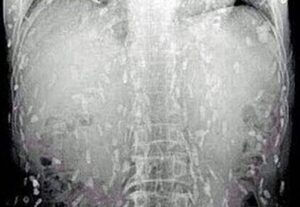

<p>Brezilyalı doktorlar, kendilerini şaşırtan bir vakanın röntgen görüntülerini paylaştı. İyileşmeyen öksürük ve baş ağrısı şikayeti olan hastanın uzun bir zamandır tenyalar tarafından tarafından organlarının delik deşik edildiği ortaya çıktı. Bilim insanları, parazit hastalıkların ölümcül olabileceğini belirterek, gıda hijyenine dikkat edilmesini istedi.</p>

<p>Bir doktorun Twitter&#8217;da paylaştığı  röntgen, her biri bir parazitin yerleşmiş  kalıntılarını temsil eden yüzlerce parlak lekeyi gösterdi.</p>

<p>Görüntüyü paylaşan Brezilya&#8217;daki Botucatu&#8217;daki Hospital das Clínicas&#8217;tan Dr. Vitor Borin de Souza, hastanın öksürük şikayetiyle geldiğini  ve durumun MRI ile rontgen taramalarında anlaşıldığını söyledi.</p>